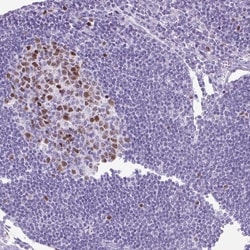

| Immunohistochemistry (Paraffin), Western Blot, Immunocytochemistry | |